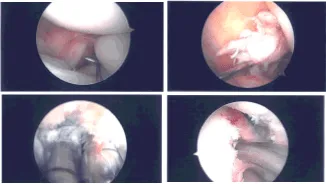

Se realizó un examen bajo anestesia que mostró laxitud del LCA o prueba de Lachman sin punto final. Se construyó un portal de entrada lateral. Se introdujo el artroscopio y se realizó un portal de entrada medial con la ayuda de una aguja espinal.

El examen de la rodilla mostró un desgarro medial en mango de cubo desde el cuerno posterior hasta la mitad del cuerpo. También mostró avulsión y lesión del ligamento cruzado anterior con colapso. El compartimento lateral no mostró desgarros ni lesiones. El compartimento patelofemoral estaba normal. Decidimos extraer el autoinjerto del cuádriceps como estábamos planeados.

Imágenes de artroscopia intraoperatoria

Mientras tanto, se insertó de nuevo un artroscopio en la rodilla. Se planificó la reparación del menisco medial del interior utilizando cánulas específicas de zona del menisco. Secuencial desde el cuerno posterior hasta la mitad del cuerpo. Todas las agujas se extrajeron de la rodilla medial.

Se cortaron las agujas y las suturas se sujetaron con un hemostato. Se realizó desbridamiento de LCA. La unión femoral del LCA se preparó usando la afeitadora. La unión tibial también se preparó usando la maquinadora.